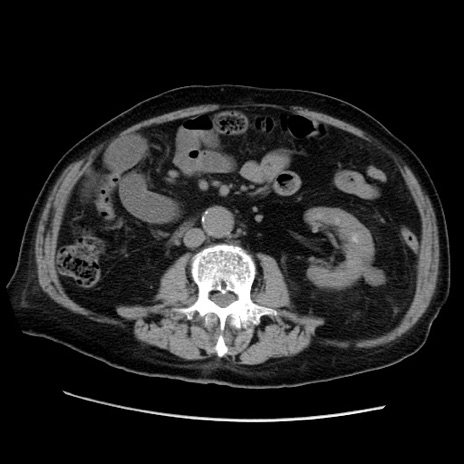

症例21(横断像)

【症例】70歳代男性

【主訴】腹痛

【現病歴】肝硬変・肝細胞癌にてかかりつけの方。約9時間前に食後より腹痛出現。症状が徐々に増悪し、嘔吐出現したため来院。

【既往歴】肝硬変、肝細胞癌(RFA、TACE後)

【身体所見】意識清明、表情苦悶様、BT 36℃、BP 129/78mmHg、P 88bpm、SpO2 97%(RA)、右上腹部から心窩部にかけて圧痛あり、反跳痛なし、筋性防御あり。

【データ】WBC 5800、CRP 0.16